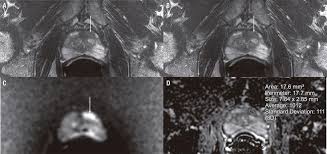

Cancers Free Full Text Correlation Between Intraprostatic Psma Uptake And Mri Pi Rads Of 68ga Ga Psma 11 Pet Mri In Patients With Prostate Cancer Comparison Of Pi Rads Version 2 0 And Pi Rads Version 2 1 Html

Cancers Free Full Text Correlation Between Intraprostatic Psma Uptake And Mri Pi Rads Of 68ga Ga Psma 11 Pet Mri In Patients With Prostate Cancer Comparison Of Pi Rads Version 2 0 And Pi Rads Version 2 1 Html from www.mdpi.com